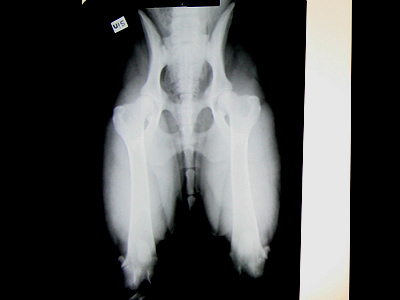

länge för. Klara, Jizza, Helly och Tage röntgades idag. Tyvärr hann

jag bara med att fota på Jizza och Tages röntgen.

Nu är det bara att hålla alla tummar och tassar att det blir ett bra

resultat